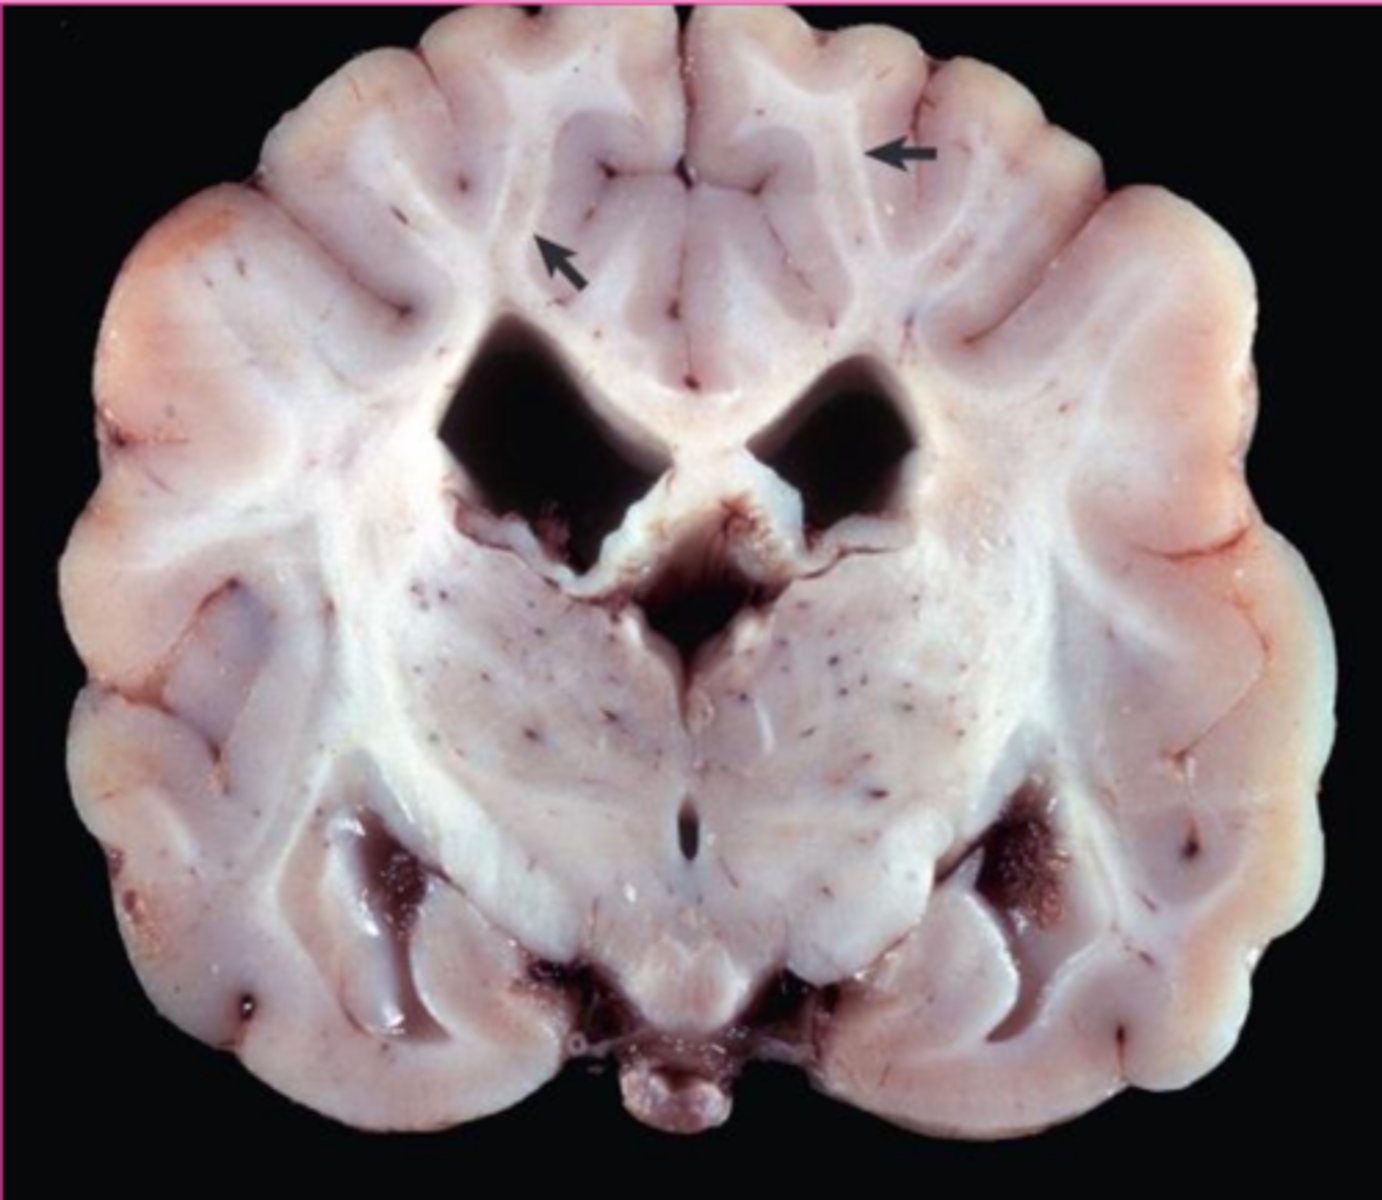

Tay-sachs disease

what?

<p>what?</p>